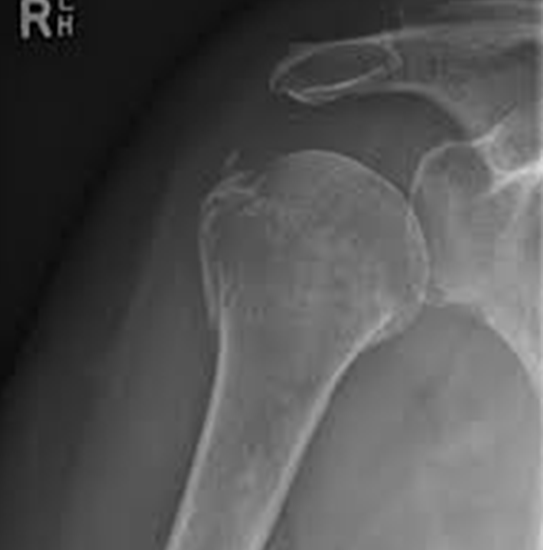

What is an X-ray Humerus AP/LAT View Test?

An X-ray of the humerus is a non-invasive diagnostic procedure that uses a minimal dose of radiation to picture the upper arm bone (the humerus) and the soft tissues surrounding it (skin and muscles).